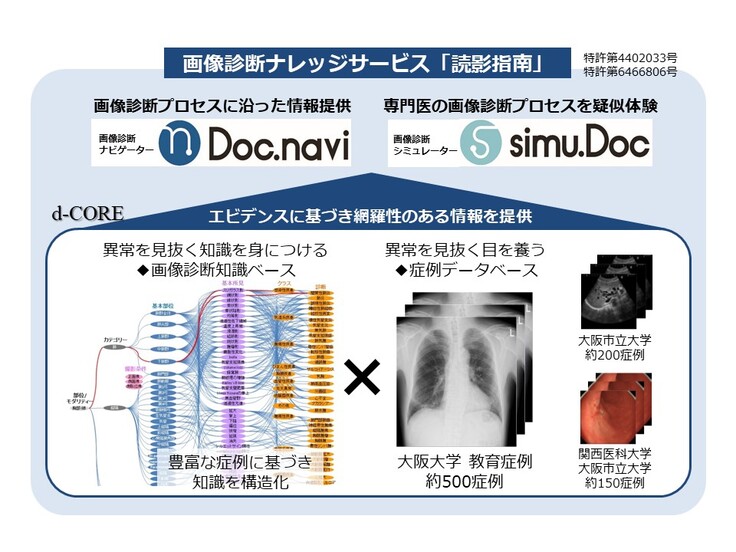

メディカル指南車ではコロナ禍以前から画像診断における社会課題に着目し、大学病院が保有する豊富な知識・経験をコンピュータ(AI)に覚え込ませ、そのAIを用いることにより「専門医」が不在で症例が不足している施設でも効率的に画像診断の精度向上をサポートができるサービスを開発してきました。

具体的には、大学病院の膨大なデータを分析し、知識情報処理技術を応用して「画像診断知識ベース」として画像診断に必要な要素(語彙)同士の関係からコンピュータ(AI)に画像診断の知識と経験を覚え込ませることに成功しました。すなわち何万通りの「データ」からコンピュータが理解できる「知識」への進化が実現できました。同時に大学病院の診断価値の高い症例を抽出し、患者属性、確定診断、「画像診断知識ベース」との相互関係を定義することにより、症例をコンピュータ(AI)に理解させることに成功しました。

その成果を利用して開発したメディカル指南車の”画像診断ナレッジサービス「読影指南」”は、「専門医」以外の医師や診療放射線技師に対して効率的に画像診断の精度向上をサポートできるサービスを提供します(下図)。画像診断ナレッジサービス「読影指南」は、単に特定の疾患の症例を理解するだけではなく、体系的に画像診断を理解して臨床現場で応用することができるこれまでにないサービスです。